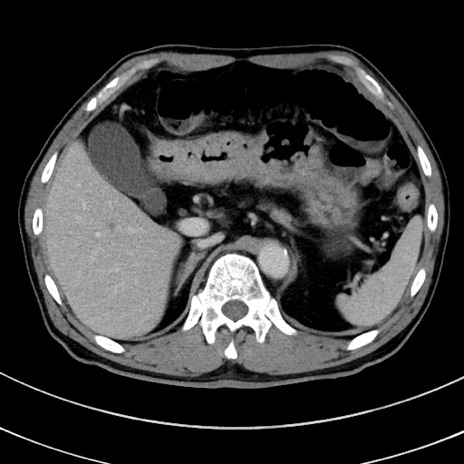

症例8(横断像)

【症例】 60歳代男性

【主訴】 黒色吐物

【現病歴】 4日前から嘔気自覚、2日前の朝食後にも嘔気あり、自分で手で嘔吐反射起こし嘔吐したところ血が混ざっていたため受診。

【既往歴】 5年前汎発性腹膜炎を伴う急性虫垂炎で手術、高血圧、前立腺肥大症、高脂血症

【身体所見】 腹部正中に手術癩痕あり 腹部平坦・軟圧痛なし膨満感あり

【データ】WBC 8400、CRP 4.54